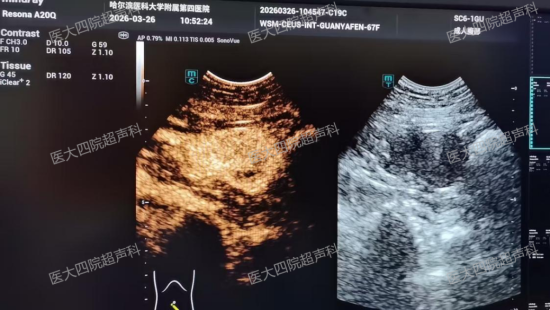

五年来,患者关女士(化名)辗转求医,多次做胃镜和肠镜、全腹CT检查,始终未能找到贫血根源。来到哈医大四院就诊后,超声科王思明医生详细追问病史,得知患者有偶发黑便及长期严重贫血,凭借专业敏感度,为其进行胃肠道超声检查。检查中发现小肠肠壁上一枚实性外突肿瘤,随着体位变化位置不停改变。荆慧主任为其实施了小肠肿瘤超声造影检查,造影显示:肿瘤呈不均匀低回声,边界清晰,内部血流丰富,动脉期快速高增强、延迟期廓清缓慢——符合小肠间质瘤的典型影像特征。肿瘤从肠壁向外生长,侵蚀了肠壁血管,五年顽固贫血的“元凶”得以锁定。

小肠病灶超声造影符合小肠间质瘤影像特征